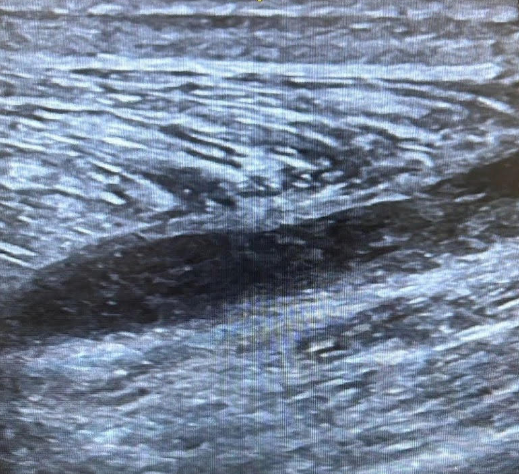

Foot Doesn’t Work Right

A 35-year-old male felt a painful “pop” in his posterior left lower leg while playing football. Afterwards his “foot didn’t work right anymore.” X-ray of the left ankle and tib/fib are normal but he is unable to ambulate. You place an ultrasound over the area of maximal tenderness and discover the following: